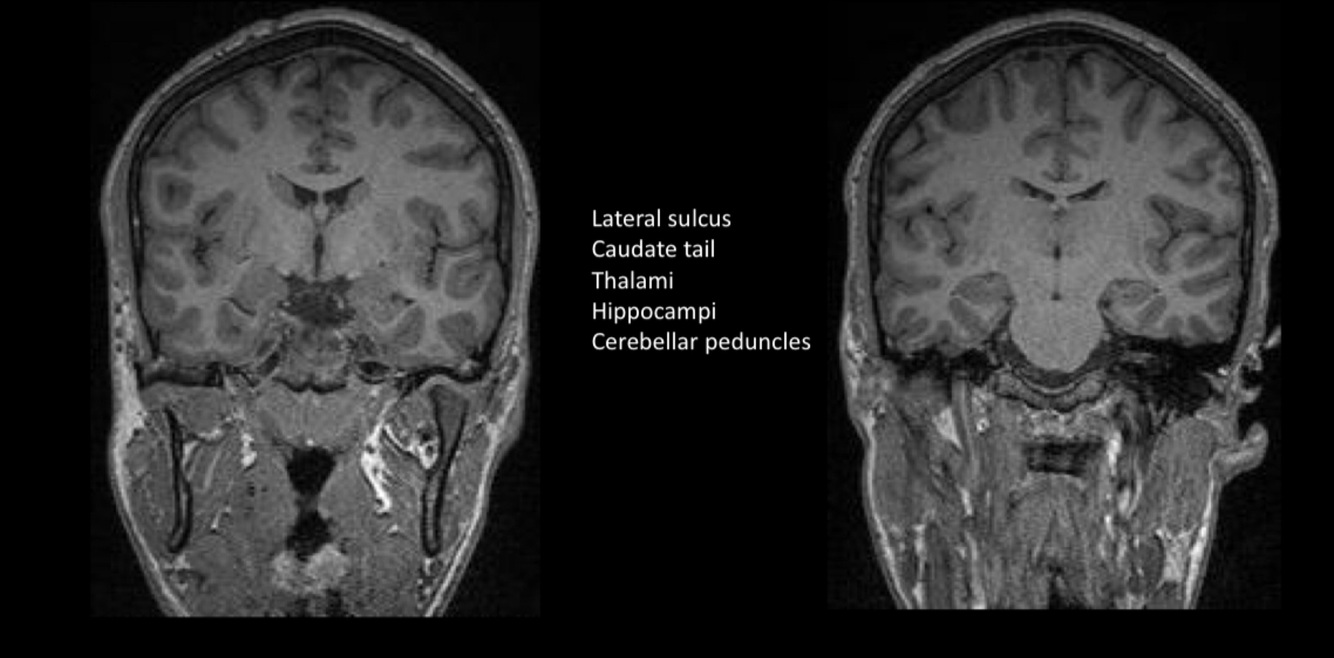

In this image we can see the…

Sylvian sulcus